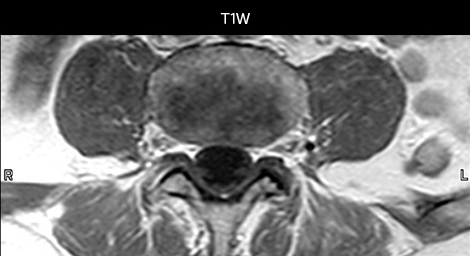

Examen de routine du rachis cervical

Ce patient s’est présenté avec des maux de tête aggravés par la flexion du cou, et on constate une malformation de Chiari de type I avec des amygdales cérébelleuses basses ainsi qu’un changement thrombolytique cervical dégénératif.